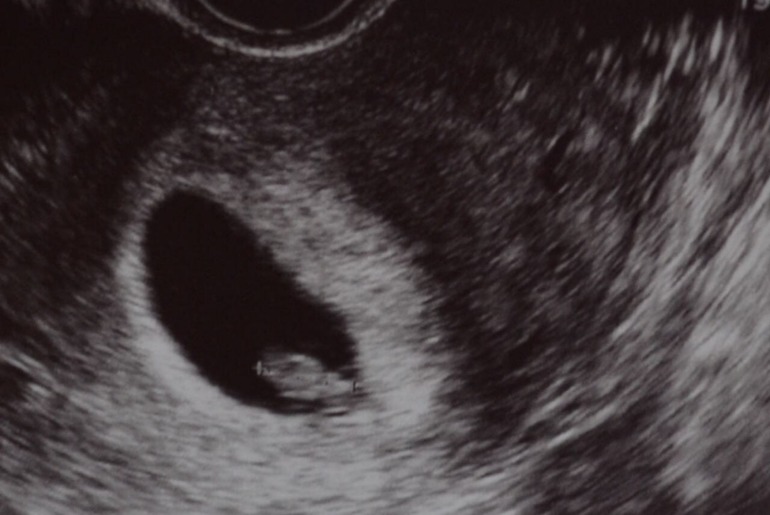

Нашелся... нашелся мой партизан. 10 мм целых. И желточный мешочек и сердце бьется. Все есть!!!! Сердечко правда послушать не дали, но снимок дали как кардиограмма такой. Я сижу, дебильно хихикаю от счастья, говорю врачу:- ну что-ж вы меня так напугали? А она мне: -да я вообще регресс подозревала, не хотела вас расстраивать. Если бы в ЖК пошли, выскребли бы все уже. А так немного понервничали, зато все хорошо. Срок по

узкартине - 7 недель.

Девочки, миленькие, по КД уже шесть недель. Была сегодня на узи. Плодное яйцо в матке 11 мм, ни эмбрион, ни желточный мешочек не визуализируются. Сердцебиения не слышно. После долгого неуверенного мычания и вопросов типа: "а предыдущая беременность чем закончилась?" и "а осложнений не было?" врач протянула "ну, может срок маленький....". Поставила срок 4-5 недель. Назначила повторное через две недели. А-А-А-А как прожить их, с ума сойду же?(((